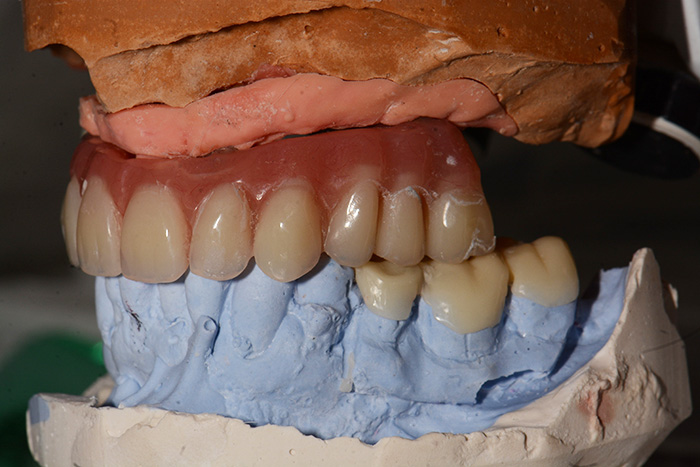

Fig. 1 : Modèle d’étude et mise en articulateur en utilisant un arc facial, ce qui va permettre au prothésiste de réaliser une prothèse totale immédiate ajourée en palatin de 13 12 11 21 22 23, en réaugmentant la DVO et en suivant les principes d’occlusion de Planas (Réhabilitation neuro-occlusale RNO, P. PLANAS. S.A. 1987) pour amener le patient à une occlusion unilatérale alternée par des latéralités en fonction de groupe et surtout avec des AFMP (angle fonctionnel masticateurs de Planas) égaux.

Fig. 12 : Une gouttière a été réalisée pour coller sur les dents 35, 36 et 37 du Stellite mandibulaire afin de retrouver une DVO et une occlusion équilibrée s’inscrivant dans une courbe de Spee et de Wilson idéale.